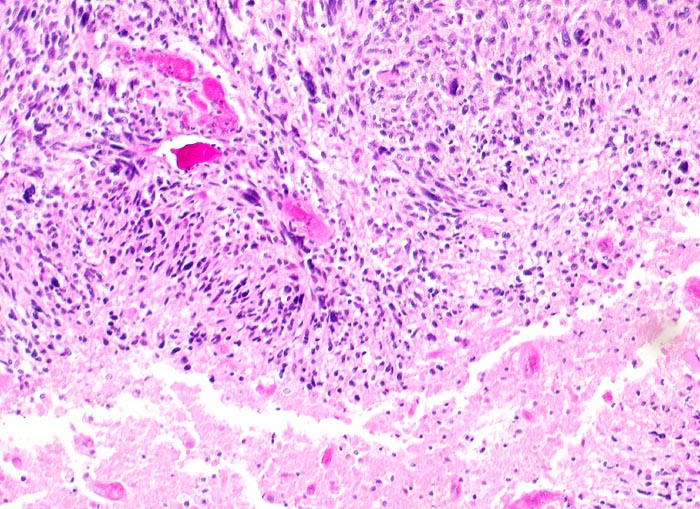

n/ Glioblastoma multiforme WHO Grad IV

Glioblastoma multiforme WHO Grad IV

Das zytologische Bild gleicht einem hochmalignen Sarkom. Die Tumorzellen sind oft in mehreren Reihen um eine Kapillarachse herum angeordnet. Das Spektrum reicht von kleinen lymphozytenähnlichen Zellen bis zu grossen zytoplasmareichen und mehrkernigen Zellen. Das Kernchromatin ist grob retikulär und die Kerne sind embryonenartig gebuchtet. Mitosen sind oft anzutreffen. Das Zytoplasma kann degenerativ bedingte Vakuolen enthalten. Den Hintergrund bildet ein Gemisch aus fibrillärer Matrix, Blut, Detritus und Kalkpartikeln.